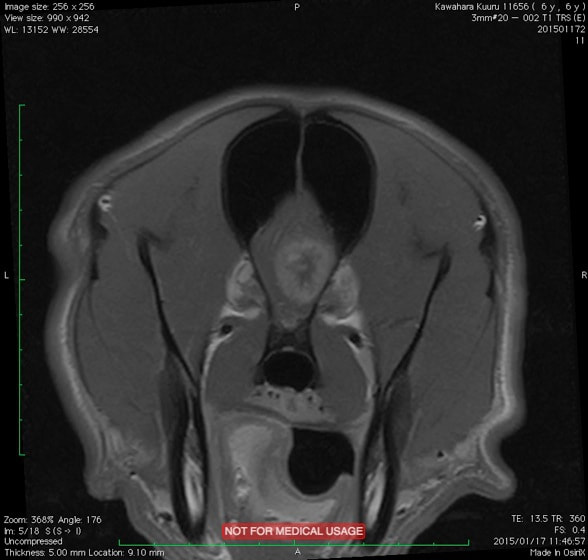

T1強調画像(造影)

FLAIR画像

Saggital画像

Coronal画像

画像は9歳のゴールデンレトリーバーの頭部MRIです。本症例は発作を主訴に来院されました。

MRI検査の結果、前頭葉に脳腫瘍が確認されました。